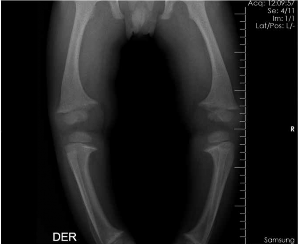

El hijo fue evaluado por el antecedente materno de raquitismo hipofofosfatémico, tiene 15 meses de edad y recibe tratamiento con aporte de fósforo Solución de Joulie 7 ml 4 veces/día (aporte de fósforo 52 mg/kg/d) y calcitriol 1 ug/día (0.5 ug C/12 horas) desde los 4 meses. A pesar del tratamiento y de tener una curva de crecimiento adecuado para edad tiene un retraso en la aparición de dientes y deformaciones en extremidades inferiores como se aprecian en las imágenes 1 y 2. Los exámenes auxiliares de la madre y el hijo al momento de la evaluación clínica inicial se muestran en la tabla 1.